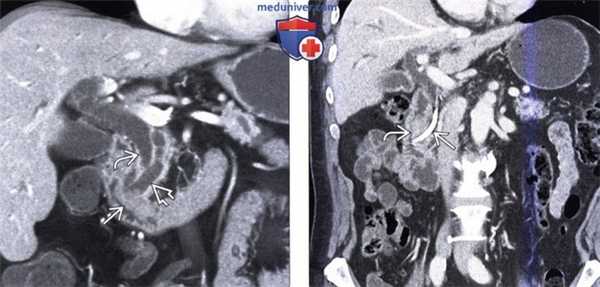

(Слева) На корональной КТ с контрастным усилением (объемный рендеринг) определяется симптом «двойного протока» на фоне обструкции общего желчного и печеночного протоков, обусловленной полиповидным объемным образованием (рак) ампулы фатерова сосочка.

(Справа) На корональной КТ с контрастным усилением визуализируется дискретное объемное образование вокруг ампулы фатеровы сосочка, в которой находится билиарный стент. Рак ампулы сложно отличить от периампулярного рака двенадцатиперстной кишки методами визуализации, но, тем не менее, лечение в обоих случаях одинаково (операция Уиппла).

(Слева) На корональной КТ с контрастным усилением в ампуле фатерова сосочка визуализируется объемное образование округлой формы, с четкими контурами, приводящее к обструкции общего желчного протока. Рак ампулы практически всегда приводит к обструкции общего желчного протока, однако обструкция панкреатического протока возникает только в 50% случаев.

(Справа) На аксиальной КТ с контрастным усилением визуализируется инвазивная аденокарцинома ампулы фатерова сосочка, возникшая из ворсинчатой аденомы. Обратите внимание на циркулярное объемное образование большого размера (в виде «огрызка яблока») двенадцатиперстной кишки, располагающееся на границе ее второй и третьей части.